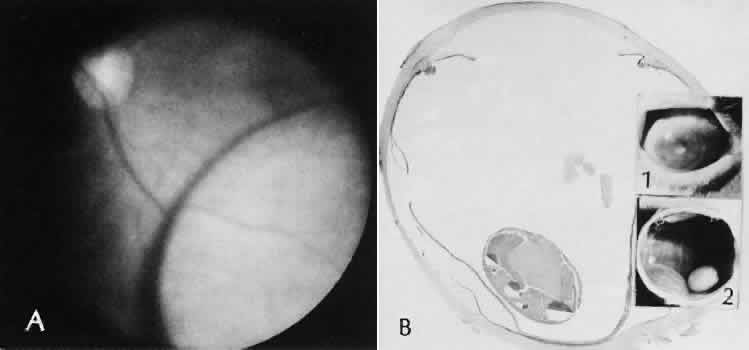

Expulsive choroidal hemorrhage (Fig. 30) is a rare catastrophic complication often resulting in total loss of the eye.93 The site of hemorrhage is probably a sclerotic choroidal arteriole where the vessel crosses the suprachoroidal space from the scleral canal. The sudden hypotension after surgical penetration of the globe causes a bending and then a rupture of the arteriole.94 Although most hemorrhages are massive and immediate, they occasionally are delayed, and some may not occur for days or weeks after surgery. Delayed choroidal hemorrhage may occur at the time of corneoscleral suture removal,95 because of clinically unapparent wound dehiscence or as a result of perforation of a corneal ulcer.

Fig. 30. A case of expulsive choroidal hemorrhage. A. Expulsive choroidal hemorrhage occurred 3 weeks after cataract surgery at the time when a limbal suture was removed. The intraocular pressure was reduced enough to allow shearing forces in the superficial choroid to tear an arteriole resulting in a high-pressure hemorrhage. B. In another case enucleated shortly after cataract extraction because of expulsive hemorrhage, accumulated blood can be identified in the suprachoroidal space. Because of the loose attachment of the choroid to the sclera, all intraocular contents were displaced toward the cataract wound. (Hematoxylin-eosin stain; × 3.)

Histologically, massive choroidal hemorrhagic detachment is associated with a retinal detachment. The retina and choroid may herniate through the scleral wound. A ruptured ciliary artery may be found in the suprachoroidal space.

Fig. 31. A case of choroidal detachment. A. By fundus reflex, a large dome-shaped mass can be seen originating from the choroid. The differential diagnosis would include uveal malignant melanoma. In this case, the clinical findings were due to choroidal detachment from the sclera because of fluid accumulating in the suprachoroidal space following cataract surgery. B. The histologic section from another case of choroidal detachment illustrates the location (arrow) and extent of the detachment. In this case the detachment extends to the region of the ciliary body limited anteriorly by the attachment of the choroid to the scleral spur. The displacement of the ciliary body will result in apparent shallowing of the anterior chamber. (Hematoxylin-eosin stain; × 6.)